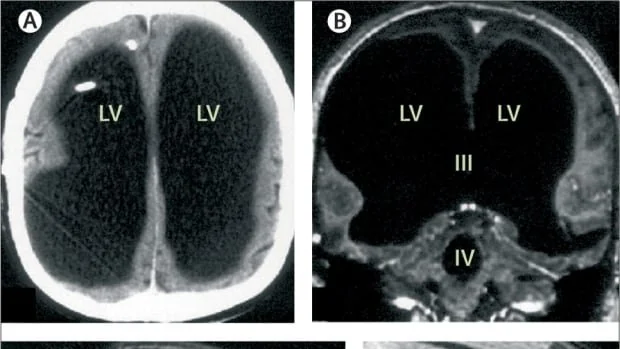

Когда у 44-летнего мужчины из Франции появилась слабость в ногах, он обратился в больницу. Именно тогда врачи сказали ему, что у него отсутствует большая часть мозга. Череп мужчины был полон жидкости, от него остался лишь тонкий слой мозговой ткани. Состояние известно как гидроцефалия.